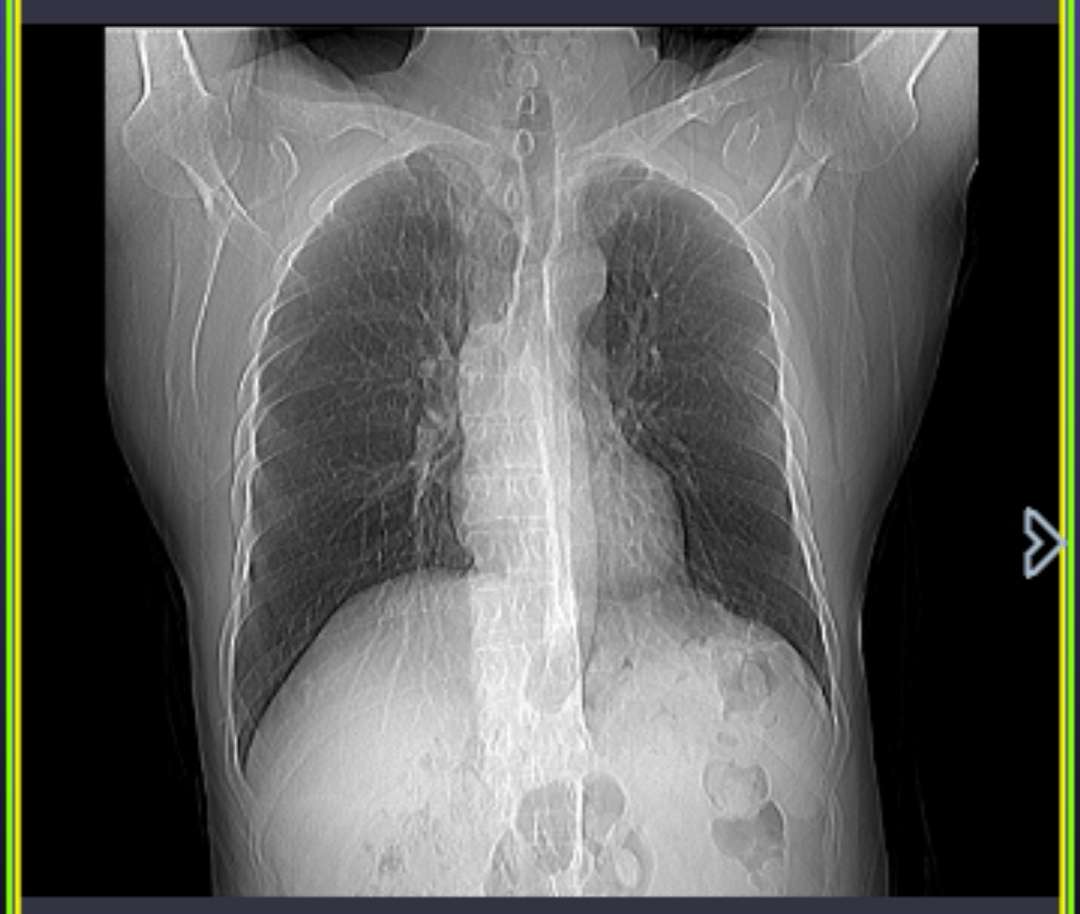

爸爸在11月确诊肿瘤大小为5.3*4.0cm,12月10号开始吃凯美纳,1月3日复查ct,肿瘤最大直径3.8cm,这边因为新冠肺炎,没能去之前的医院检查,前几天出现咳血,但是量不多,两天后就没有症状了,一开始在当地的小医院检查ct报告肿瘤变成了4.8*3.0cm,然后今天我们去了省医院检查ct报告写着肿瘤为3.8*3.0cm,跟我们吃凯美纳后第一次复查的结果差不多,但是ct还提示右侧第七肋环形异常密度影,这个是在之前的ct报告中没有提到过的,这个报告是手机中刚出来的,有没有病友能帮忙看一下是怎么回事,万分感谢。

这是今天的ct